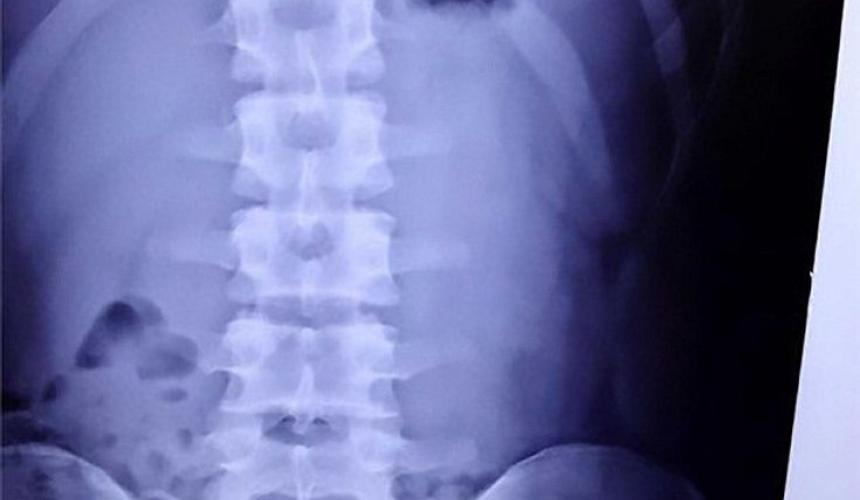

Μια νέα αμερικανική επιστημονική έρευνα για τον καρκίνο των όρχεων έρχεται στο φως της δημοσιότητας. Σε αυτήν αναφέρεται πως η πρώιμη και επαναλαμβανόμενη έκθεση ενός άνδρα σε απεικονιστικές διαγνωστικές εξετάσεις με ακτινοβολίες, όπως οι ακτινογραφίες-Χ και οι αξονικές τομογραφίες, μπορεί να αυξήσουν τον κίνδυνο εμφάνισης.

Διαπιστώθηκε ότι υπήρχε σημαντική αύξηση κατά σχεδόν 60% του κινδύνου για την εμφάνιση του συγκεκριμένου καρκίνου για όσους είχαν κάνει τουλάχιστον τρεις ακτινογραφίες και αξονικές τομογραφίες κάτω από τη μέση, σε σχέση με όσους δεν είχαν κάνει καμία. Επίσης, ο κίνδυνος ήταν περισσότερο αυξημένος για όσους είχαν κάνει τέτοιες εξετάσεις κατά την πρώτη δεκαετία της ζωής τους, σε σχέση με όσους τις είχαν ξεκινήσει μετά τα 18.